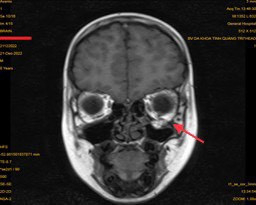

Chụp X-quang và CTScan hốc mắt thấy rõ vùng xương hốc mắt bị tổn thương. Chụp CTScan/MRI có thể cho thấy cơ bị xoắn hoặc kẹt vào xương bị tổn thương. Vỡ sàn ổ mắt rộng (>50%) hoặc vỡ sàn ổ mắt kết hợp vỡ thành trong ổ mắt rộng, sau một thời gian sẽ dẫn tới lõm mắt.

Nhân một trường hợp bệnh nhân nam 8 tuổi được chẩn đoán vỡ sàn hốc mắt trái do chấn thương. Bệnh nhân vào viện vì đau nhức mắt trái sau chấn thương, khám hạn chế vận nhãn lên trên, sụp mi, chụp MRI hốc mắt có hình ảnh vỡ sàn hốc mắt, thoát vị mô mềm hốc mắt vào xoang hàm trái.